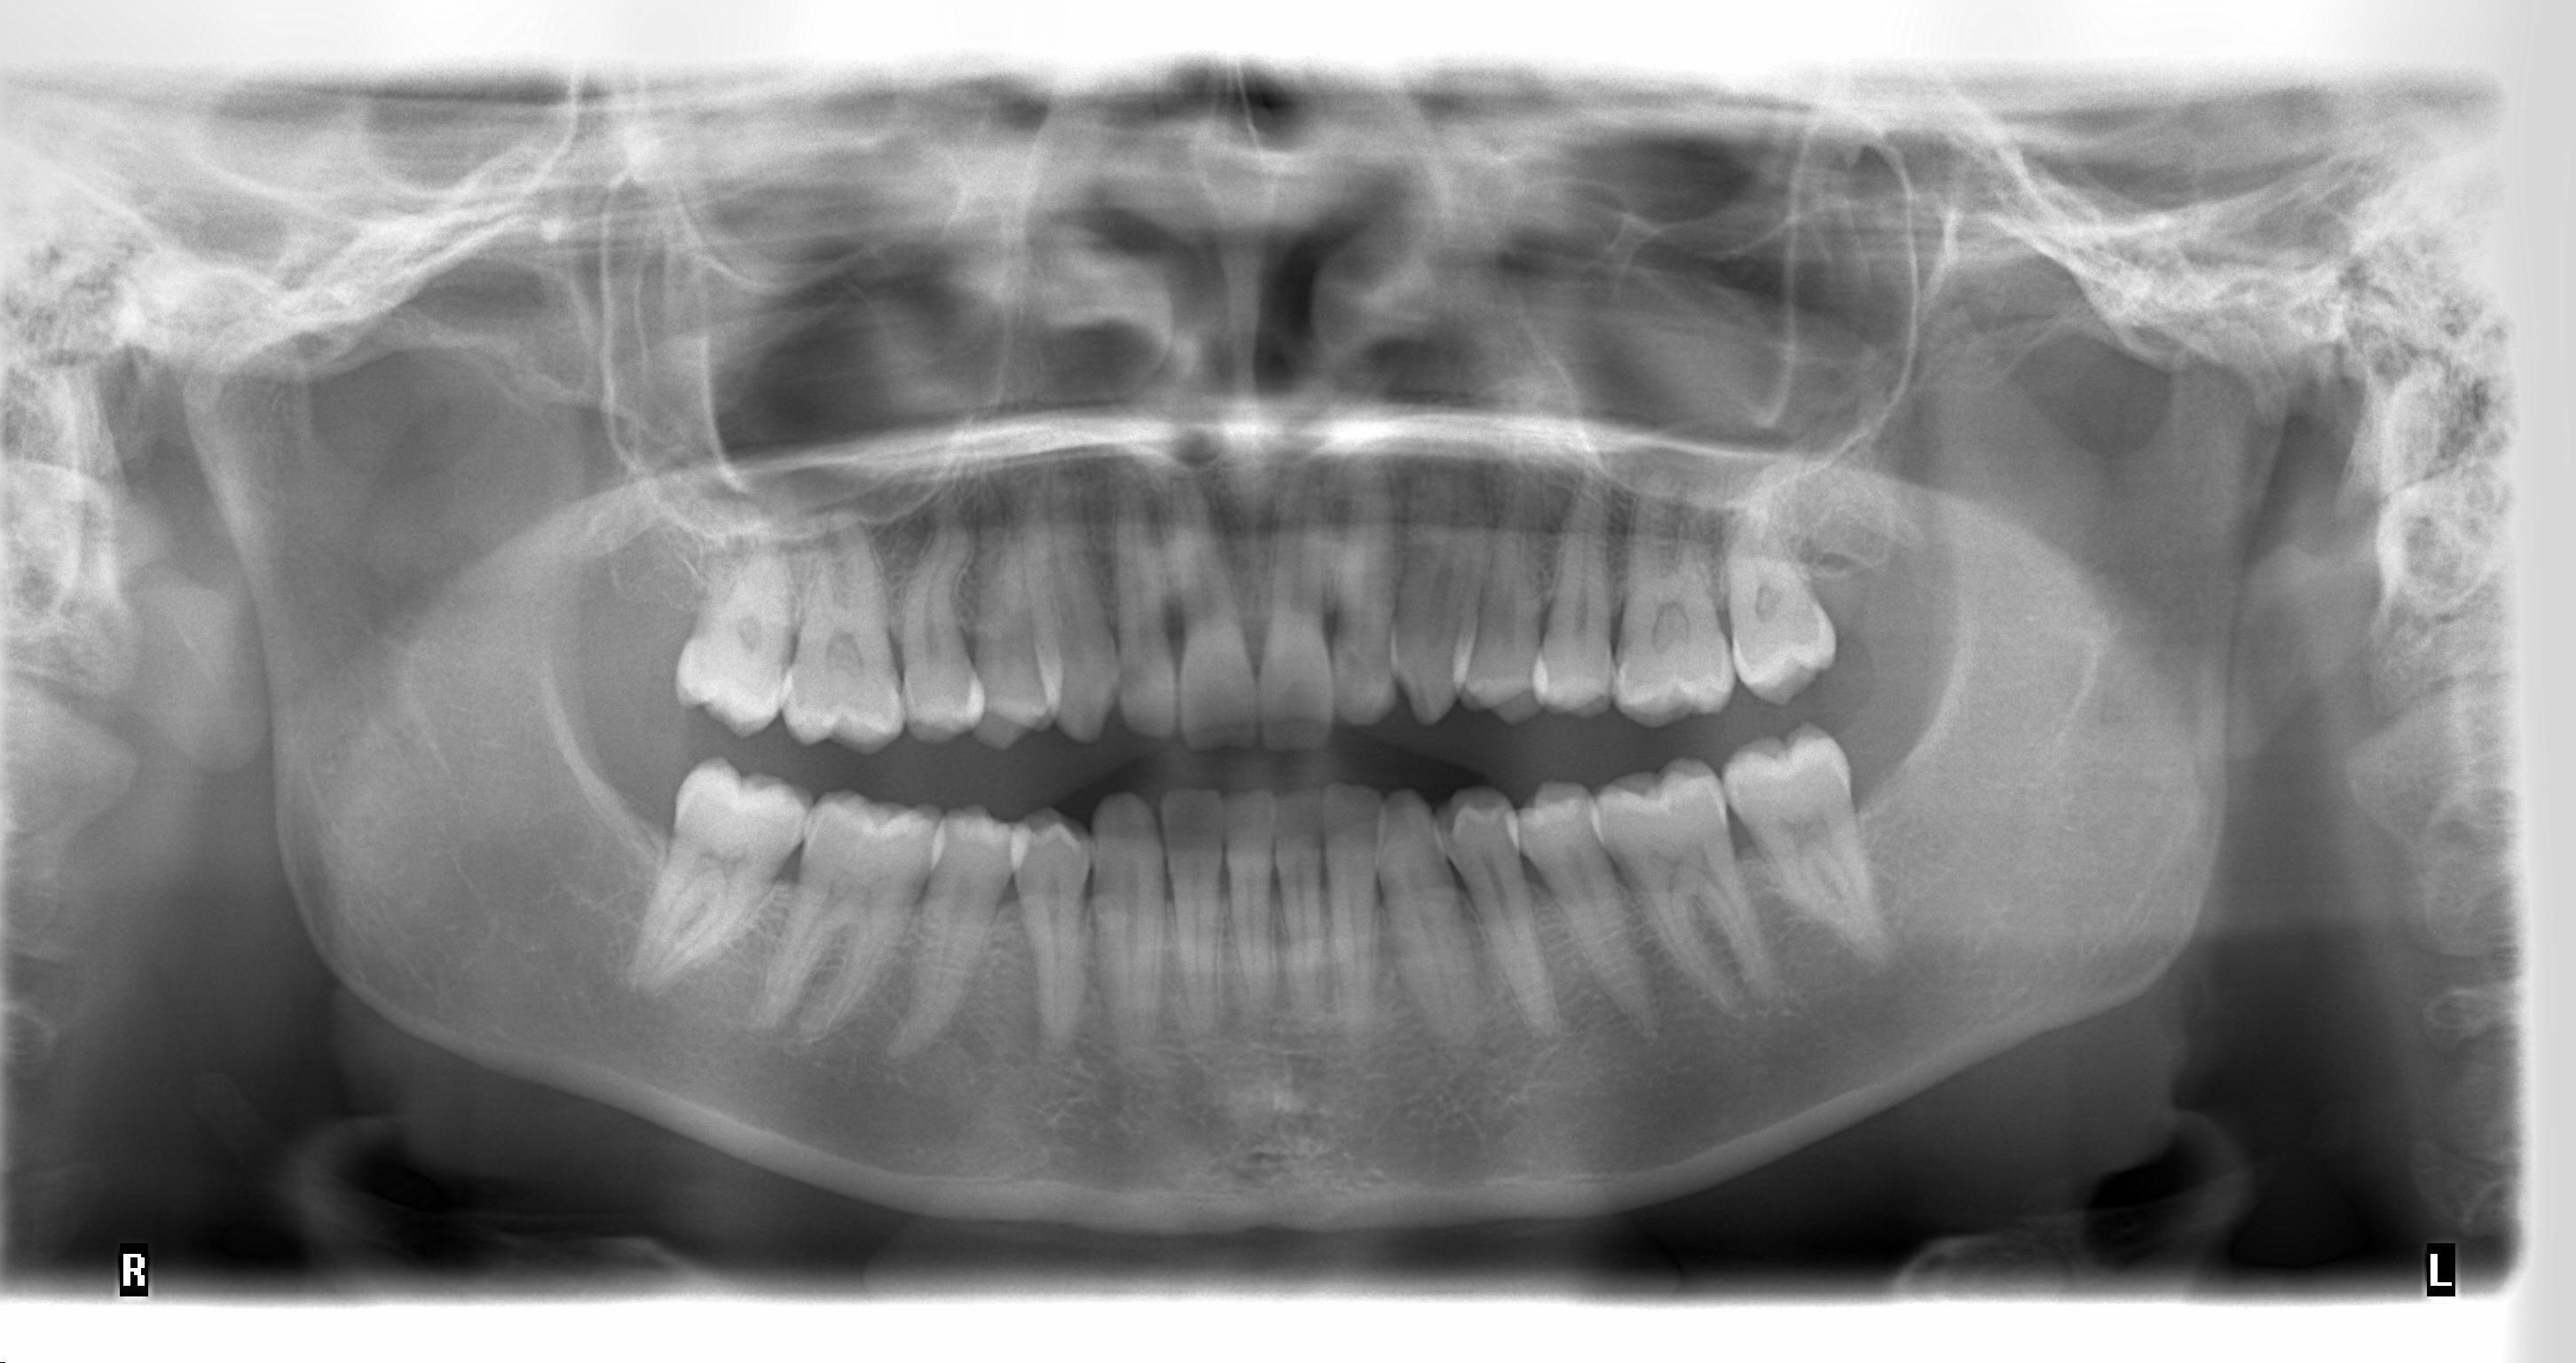

Methods: The clinical examination included extra-oral and intra-oral photographs, panoramic radiographic, lateral cephalometric, stone casts, and upper and lower arch analysis obtained from ClinCheck 3.0.The treatment planning was resolved the crowding in both upper and lower arches and the severe rotation of 33 tooth (46°) using Invisalign system as well as the canine and molar relationship, dental verticalization, adequate over jet, overbite and dental midline using the same system. The duration of the treatment was approximately eight months.

Results: In Post-treatment extra oralphotographs, no significant changes were observed at the end of the treatment. Intraoral photographs showed an important and notable improved aesthetics. The canine relationship improved slightly and molar Class Irelationship was maintained. An increase in transverse diameter was observed at the level of first premolars, second premolars and first molars. The overbite was improved. The crowding and the severe canine rotation were corrected. No obvious root resorption was radiographically evident and slight cephalometric changes.